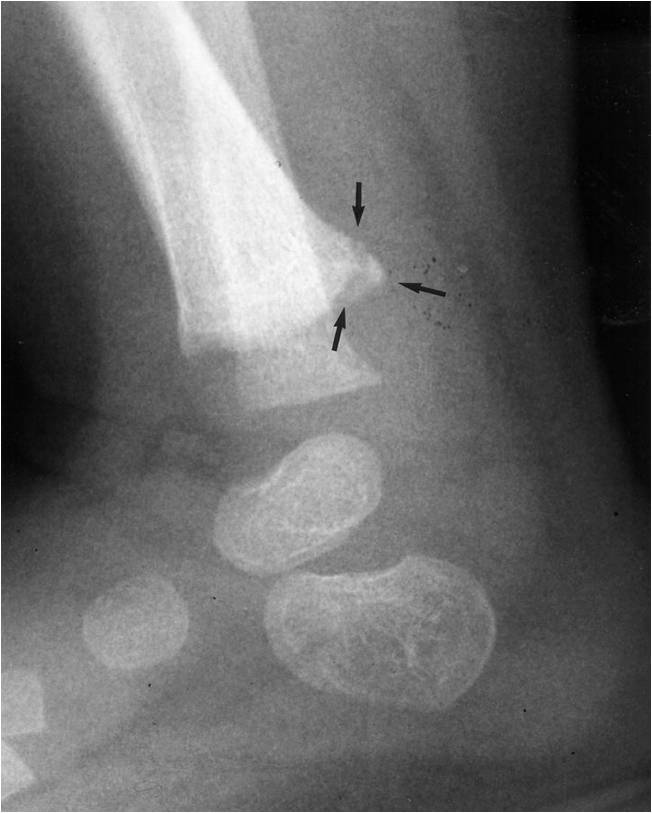

Fractura en Asa de cubo

Otra vista de la fractura en Asa de cubo